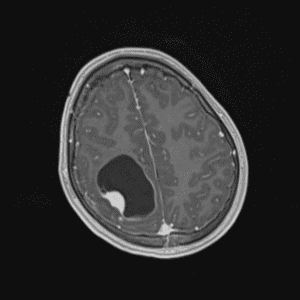

Case #33

Ganglioglioma